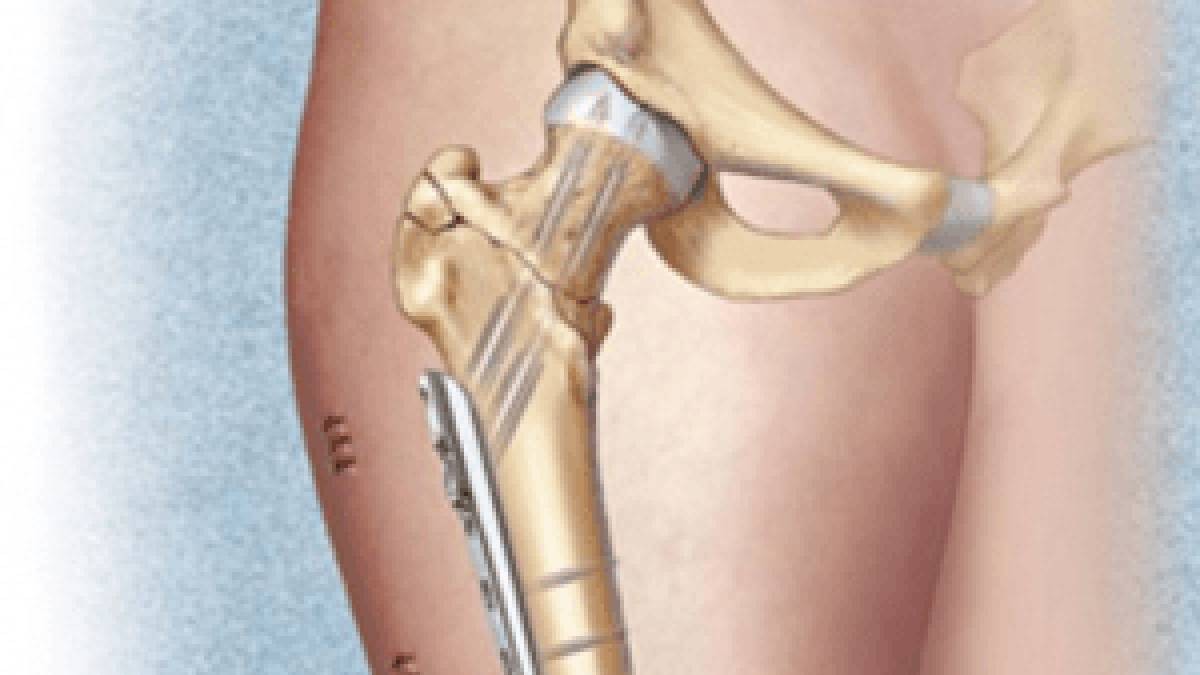

Ұршық асты және айдаршық үсті сынықтарының остеосинтезі үшін жиі бұрышты пластина немесе накладкасы бар динамикалық винт қолданылады. Ортаңғы үштен бір бөлігінің сынығында пластинамен экстрамедуллярлы остеосинтез немесе штифпен интрамедуллярлы остеосинтез жүргізіледі. Стерженьдік аппарат көмегімен фиксациялауға да болады.

Диафиз сынығының стабильды остеосинтезңне құм сағаты формалы сүйекми каналының біркелкі емес ені бөгет жасайды. Штифт тек қана каналдың арылу аймағында ғана жанасып жатады. Егер сынық аймағына сүйекми каналының тарылу аймағы сәйкес келмесе сынықшалар арасында ротационды және тербелмелі қозғалыстар тән. Стабильді остеосинтез жасау үшін сынық орнында сүйекми каналын штифтпен бірдей қылып бұрғылайды. Сәйкес диамитрлі штифт енгізіледі. Бұрғылаусыз стабильды остеосинтез үшін дистальды және проксимальды блоктайтын штифт қолданылады.

Стабильді остеосинтезден кейін гипстік таңу салынбайды. Операциядан кейін бірінші күндері аяққа дозирленген жүктемемен балдақпен жүруге болады. Толық жүктемені сынық сипаты мен фиксатор түріне байланысты рұсат етіледі.